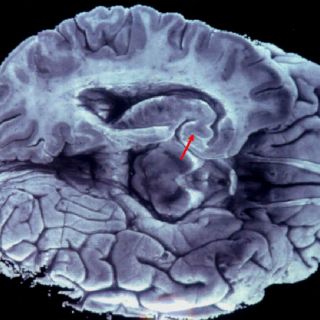

La química farmacobióloga Berenice Dionisio, alumna de quien coordina este banco, José Luna, mostró en un corte cerebral las afectaciones por esta enfermedad en la que el tamaño del cerebro se encuentra disminuido así como el hipocampo, que es el encargado de los recursos a corto y largo plazo.

Añadió que también las circunvalaciones del cerebro disminuyen debido a la muerte neuronal que se va relacionando con esta enfermedad.